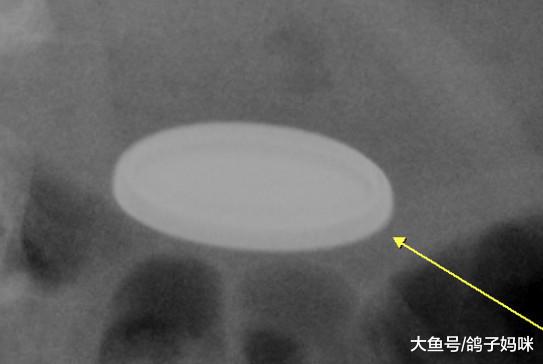

小女孩吞下异物后当下并没有不舒服,家人也未察觉异状,然而过了一阵后,小女孩开始腹痛,告诉妈妈,自己吞了一枚硬币。妈妈当下相当紧张,急忙带孩子到急诊,急诊医生简单询问事发状况后,立即安排腹部X光检查,结果发现吞进肚子里的并不是硬币,而是危险性较高的钮扣型电池,于是紧急联络小儿消化科医生,利用消化道内视镜,将电池取出。